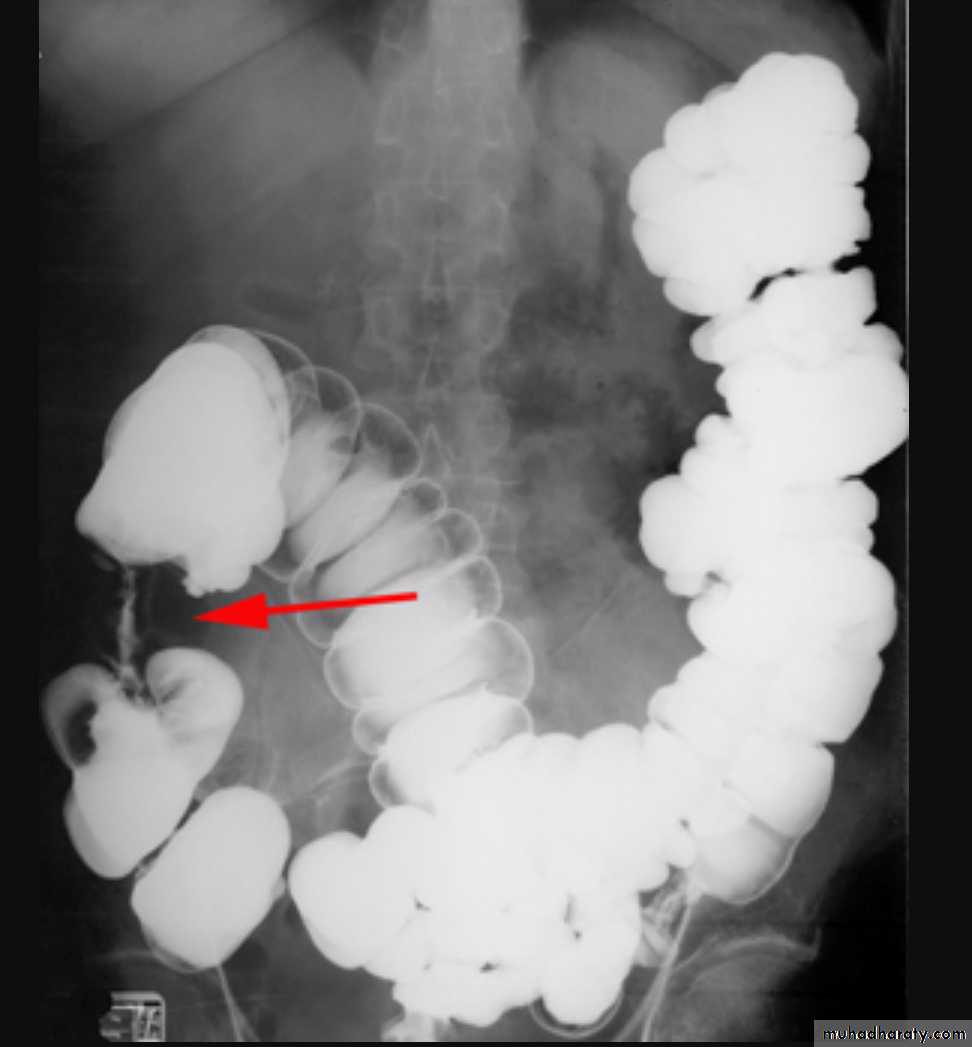

Intussusceptions occurs when one segment of bowel is pulled into itself (or a neighboring loop of bowel) It is an important cause of an acute abdomen in childrenIntussusceptions may also occur in the adult population where it is usually caused by a focal lesion acting as a lead point.

Radiographic features

Intussusceptions can occur essentially anywhere, in children there is a strong predilection for the ileo colic region

contrast enema

A contrast enema remains the gold standard, demonstrating the intussusceptions as an occluding mass prolapsing into the lumen, giving the "coiled spring ” appearance .The main contra-indication for an enema is a perforation

Contrast enema is diagnostic & therapeutic